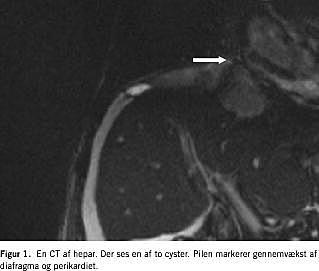

En 75-årig mand blev henvist med trykkende fornemmelse over højre kurvatur, dyspnø og hosteanfald af få ugers varighed. Ved første kontakt var patienten let ikterisk, og der var mistanke om ascites. En CT af abdomen viste to delvis cystiske processer med forkalkninger i venstre leverlap (Figur 1 ). Der var ingen galdestase. Der blev desuden påvist højresidig pleuraeksudat. Biokemisk fandtes der normale transaminaser, basiske fosfataser var forhøjet til to gange det øvre normalområde, bilirubin var på 153 μ M og protrombin 0,5, men der var ingen eosinofili. Serologi for EG var positiv, en leverbiopsi blev foretaget, men resultatet bidrog ikke til afklaring af tilstanden.

Ved en efterfølgende sektion blev det påvist, at den multilokulære ekinokokcyste havde penetreret diagfragma og perikardiet med indvækst i højre atrium.